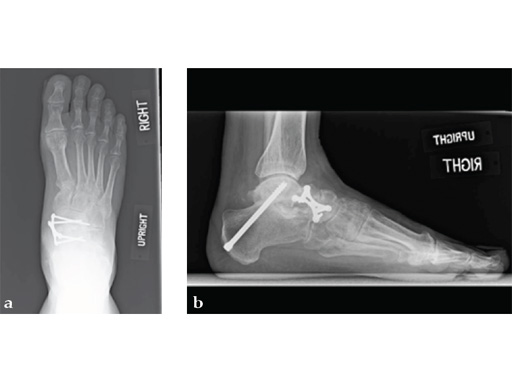

Case 5: First TMT, straight fusion and TMT fusion plates

A 46-year-old obese woman with coronary artery disease had sustained a Lisfranc injury while performing an exercise program. She was unable to weight bear and used an electric scooter.

In an effort to restore her ability to exercise and taking into consideration her body weight and upper extremity weakness, a decision was made to use the variable angle locking compression plate. These postoperative x-rays were obtained at 3 months, one month after beginning weight bearing. The patients pain was reduced and she was able to resume a progressive exercise program after 4 months following surgery.

Case provided by Michael Castro, Scottsdale, Arizona

Case 7: VA -locking X-plate

A 49-year-old woman had extreme pain in the talonavicular joint.

Case provided by Andrew Sands, New York, New York, USA

As isolated fusion of the talonavicular joint is often hard to achieve, a 4.0 mm lag screw a plus X-plate was used (see Fig. 2a-c).

Fusion of the talonavicular joint while saving the rest of the hindfoot complex motion was achieved (see Fig. 4a-c).